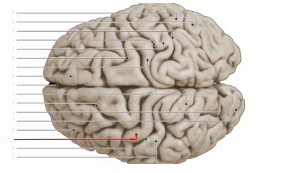

lobus frontalis

lobus parietalis

lobus occipitalis

lobus temporalis

gyrus precentralis

gyrus postcentralis

sulcus centralis

sulcus lateralis

fissura longitudinalis cerebri